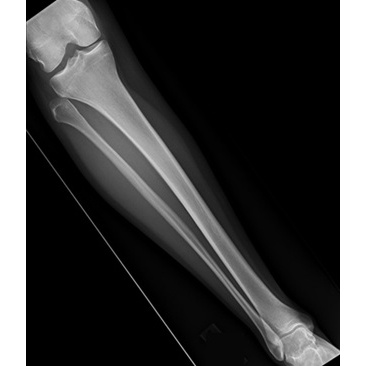

The patient reported acute onset of right lateral knee pain after being slide-tackled during a soccer match five days earlier. She experienced a varus force to her knee as she went for the ball. She reported a sensation of "popping out" at the lateral aspect of her knee at the time of injury. She stated that she had a visible deformity noted to the lateral inferior aspect of her right knee, which was self-resolved by the time she presented to a local ED for initial evaluation. She did not recall exactly how or when it reduced. She was unable to bear weight immediately after the injury. In the ED, radiographs were obtained Case Photo #1 Case Photo #2 Case Photo #3 Case Photo #4 which were negative for acute fracture or dislocation. The patient did not recall the diagnosis, but was recommended a compression wrap, crutches, and analgesics. She was advised to follow up with Sports Medicine. She presented to the Sports Medicine clinic with continued right lateral knee pain with weight-bearing, knee instability, and right anterolateral ankle pain. She reported minimal knee or ankle swelling. She denied symptoms of catching, clicking, locking, skin changes, or lower extremity paresthesias. She had no prior history of injury to the right knee.